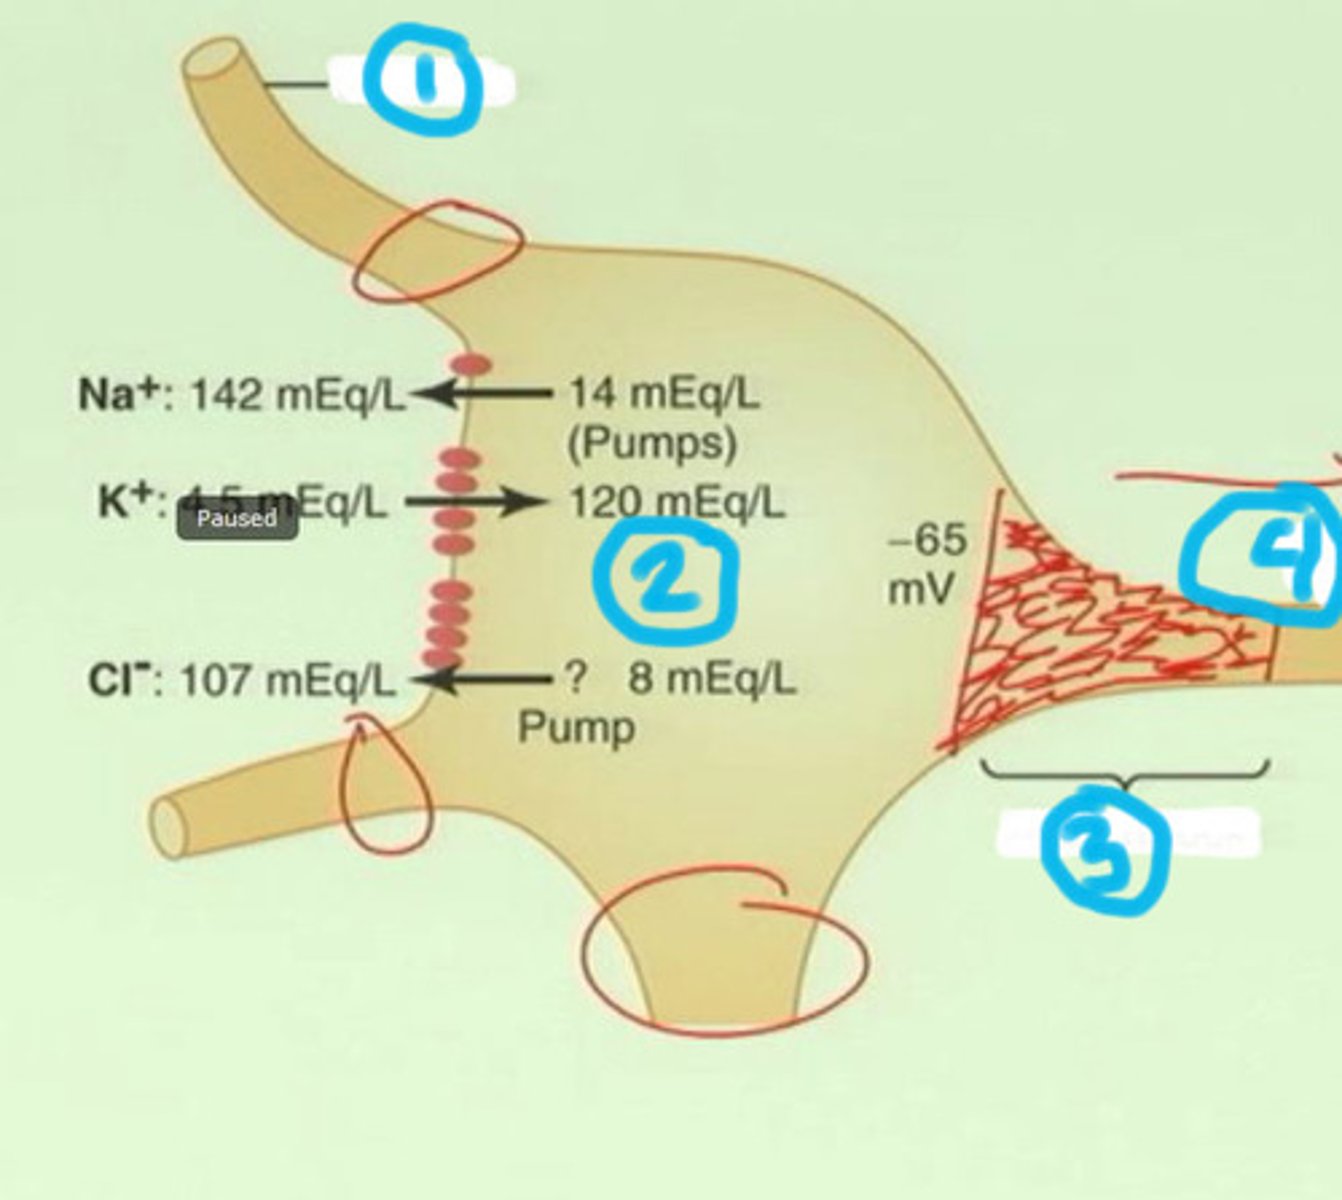

Threshold

the membrane voltage that must be reached in an excitable cell (e.g., neuron or muscle cell) in order to generate an action potential

Depolarization

a rapid rise in potential in a neuron triggered by the opening of sodium ion channels within the plasma membrane (a positive value)

Resting potential

the state of the neuron when not firing a neural impulse

Multiple sclerosis (MS)

a degenerative disease caused by destruction of the myelin sheath on neurons in the CNS characterized by sclerotic patches along the brain and spinal cord